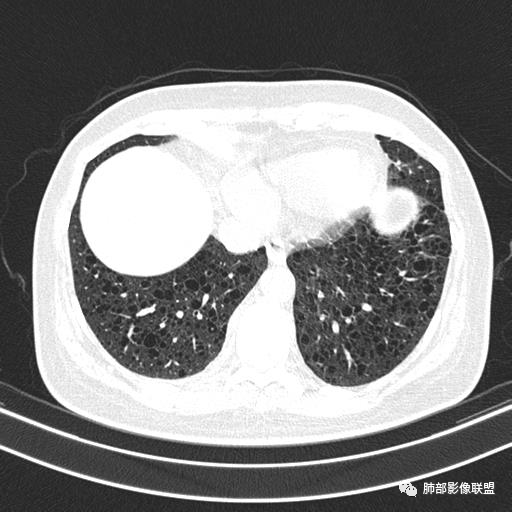

CT表现:双肺弥漫大小不等的薄壁囊腔,囊壁<2mm,外形规则,血管影多位于囊腔周围,囊腔之间肺组织正常,随着疾病进展到晚期,囊腔变大、增多,不可胜数,囊腔可融合成较大的囊,与肺气肿相似,形成间质性肺纤维化。部分病例可出现结节影。

1.小叶中心性肺气肿:上肺为主,无壁,中央见小血管影,位于小叶核心周围,部分血管可推移到边缘,周围肺组织正常

CT表现:早期阶段以结节为主,小结节分布于小叶内、支气管血管束旁及小叶间隔,囊腔形态不规则,呈分支状、两叶或三叶,大小不一,囊壁厚薄不均,主要以中上肺受累为主,双侧肋膈角往往不受累,终末期过度充气及广泛囊腔形成网状纤维化或终末肺气肿,也可导致自发性气胸。

是一种罕见、良性的淋巴组织增生性疾病,组织学上是细支气管周围及肺间质内弥漫性淋巴细胞浸润为特征,特发性LIP罕见,常继发于结缔组织病(如干燥综合征、RA、SLE),免疫抑制状态(如HIV)有关,CT表现:双肺散在多发薄壁囊腔和小叶中心结节,囊腔沿血管支气管束周围间质分布,周围有磨玻璃密度影(反应出弥漫性间质炎症),小叶间隔和支气管血管束增厚。

临床诊断BHD综合征需要满足一个主要或两个次要标准。主要标准包括:1、皮肤上至少发现5个纤维滤泡瘤,至少1个组织学证实;2、致病的FLCN种系突变阳性。次要标准:1、多发肺囊肿,双侧基底部,有或无自发性气胸;2、肾癌,起病早(<50岁)或多灶性或双侧;3、 BHD综合征一级亲属。BHD主要影像表现特征:1、两肺内肺囊肿:80%以上的BHD患者会出现肺内囊肿,且倾向于基底部近胸膜下分布,特别是纵膈侧肺膜下,囊肿形状不规则、囊肿可大可小,肺内囊肿多毗邻肺下动脉或静脉近端,胸部CT上囊肿分布和特点对诊断有提示意义。2、继发自发性气胸:BHD患者发生气胸风险是正常人的5倍,BHD患者的气胸发生率约为 1/4,气胸复发率则高达59%。3、肾肿瘤:(常为双侧性、倾向于嫌色细胞组织学亚型)4、皮肤表现(为面、颈部纤维性毛囊瘤、毛盘瘤)